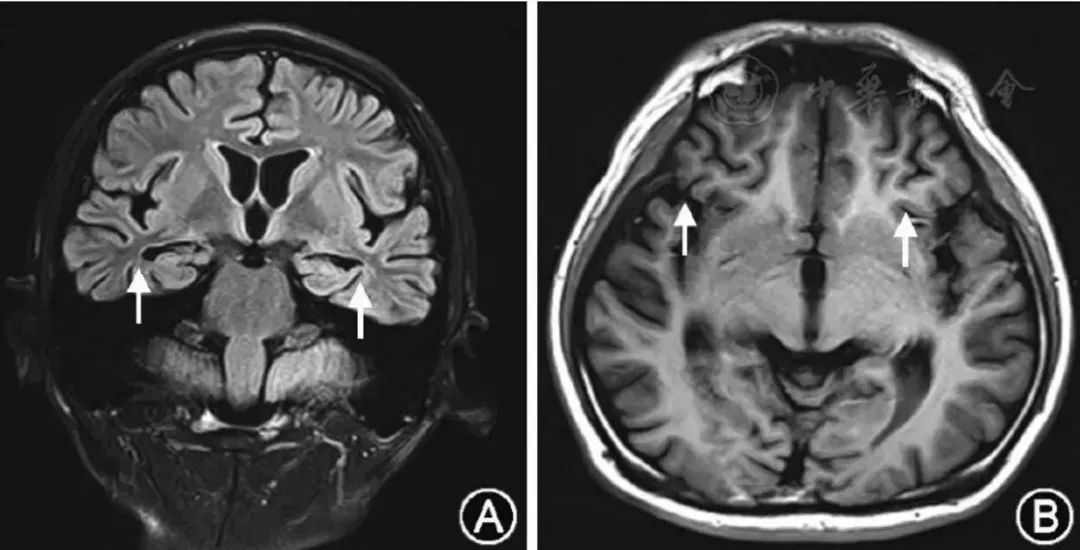

患者21岁,智能减退1年,加重伴行走不稳10天,双手抖动,生活不能自理。同型半胱氨酸(Hcy)>80 μmol/L。患者2017年11月24日头颅磁共振成像如下。

2017年11月28日头CT和12月5日复查头CT如下:

患者确诊为晚发型甲基丙二酸尿症(MMA)伴高同型半胱氨酸血症(cblC型)并发脑出血。本病由于甲基丙二酸单酰辅酶A变位酶(MCM)缺陷或其辅酶钴胺素的缺陷所致,属于常染色体隐性遗传疾病。表现为单纯的MMA或晚发型MMA伴高同型半胱氨酸血症(MMAHC),晚发型MMAHC是我国MMA患者的主要生化表型。MMAHC患者甲基丙二酸和同型半胱氨酸在体内蓄积,导致神经、血液、肝脏、肾脏等多系统损伤。患者MRI表现为广泛的大脑白质疏松,在T2WI相上出现明显的高信号,在疾病的晚期出现白质萎缩和脑室扩大。而单纯的甲基丙二酸尿症患者则以双侧基底节,尤其是苍白球的病变多见,在MRI表现为明显的长T2信号,可伴内囊后肢受累。合并同型半胱酸血症的甲基丙二酸尿症由于甲基基团的减少和异常脂肪酸代谢产物毒性作用,可能是导致患者脱髓鞘病变和白质损害的原因。MMAHC并发脑出血临床少见。